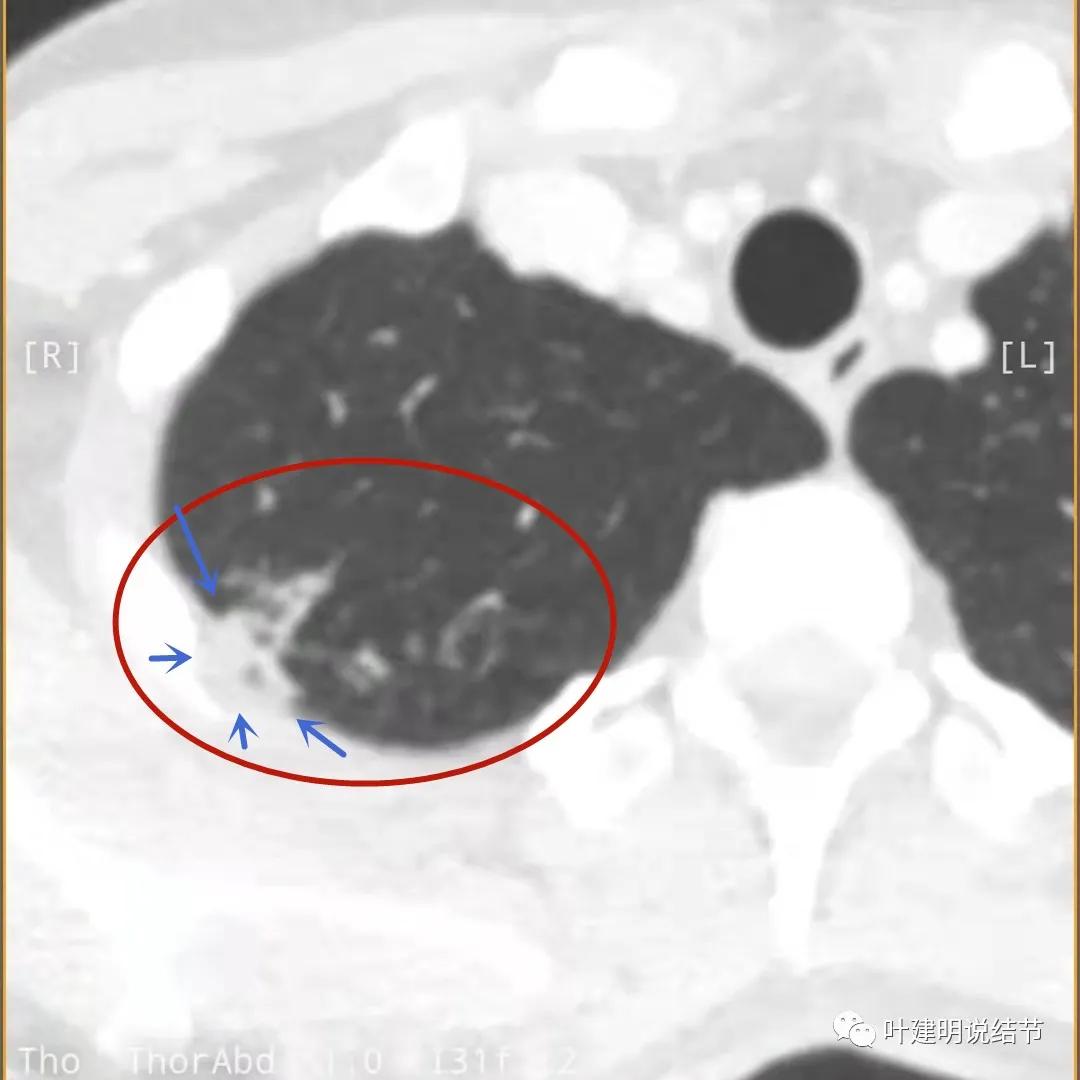

我们再来看薄层的CT图像:

病灶出现,模糊的磨玻璃影

部分密度过高,且呈条状

邻近胸膜有增厚(蓝色箭头),主病灶边界较清(红色箭头),实性部分密度过高(粉色箭头),旁边有磨玻璃影,散且模糊(砖色箭头)

邻近胸膜有增厚(蓝色箭头),主病灶实性部分密度过高(粉色箭头),旁边有磨玻璃影,散且模糊(砖色箭头)

邻近胸膜有增厚(蓝色箭头),主病灶实性部分密度过高(粉色箭头),旁边有磨玻璃影,散且模糊(砖色箭头),病灶有空腔(黄色箭头)

主病灶边界较清(红色箭头),实性部分密度过高(粉色箭头),病灶边缘向内凹,缺乏膨胀性(桔色箭头),病灶有空腔(黄色箭头)